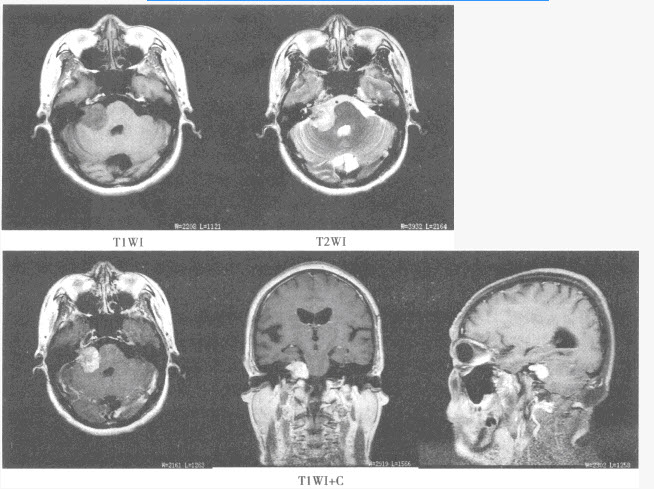

5、单项选择题

患者,女,50岁,因头晕半年来院检查,影像检查如下图。

A.星形细胞瘤

B.少突胶质细胞瘤

C.室管膜瘤

D.脑膜瘤

E.转移瘤

F.脑囊虫病

7、单项选择题

A.脑膜尾征

B.钙化

C.均匀强化

D.发病部位

E.周围水肿明显

F.以上都不是